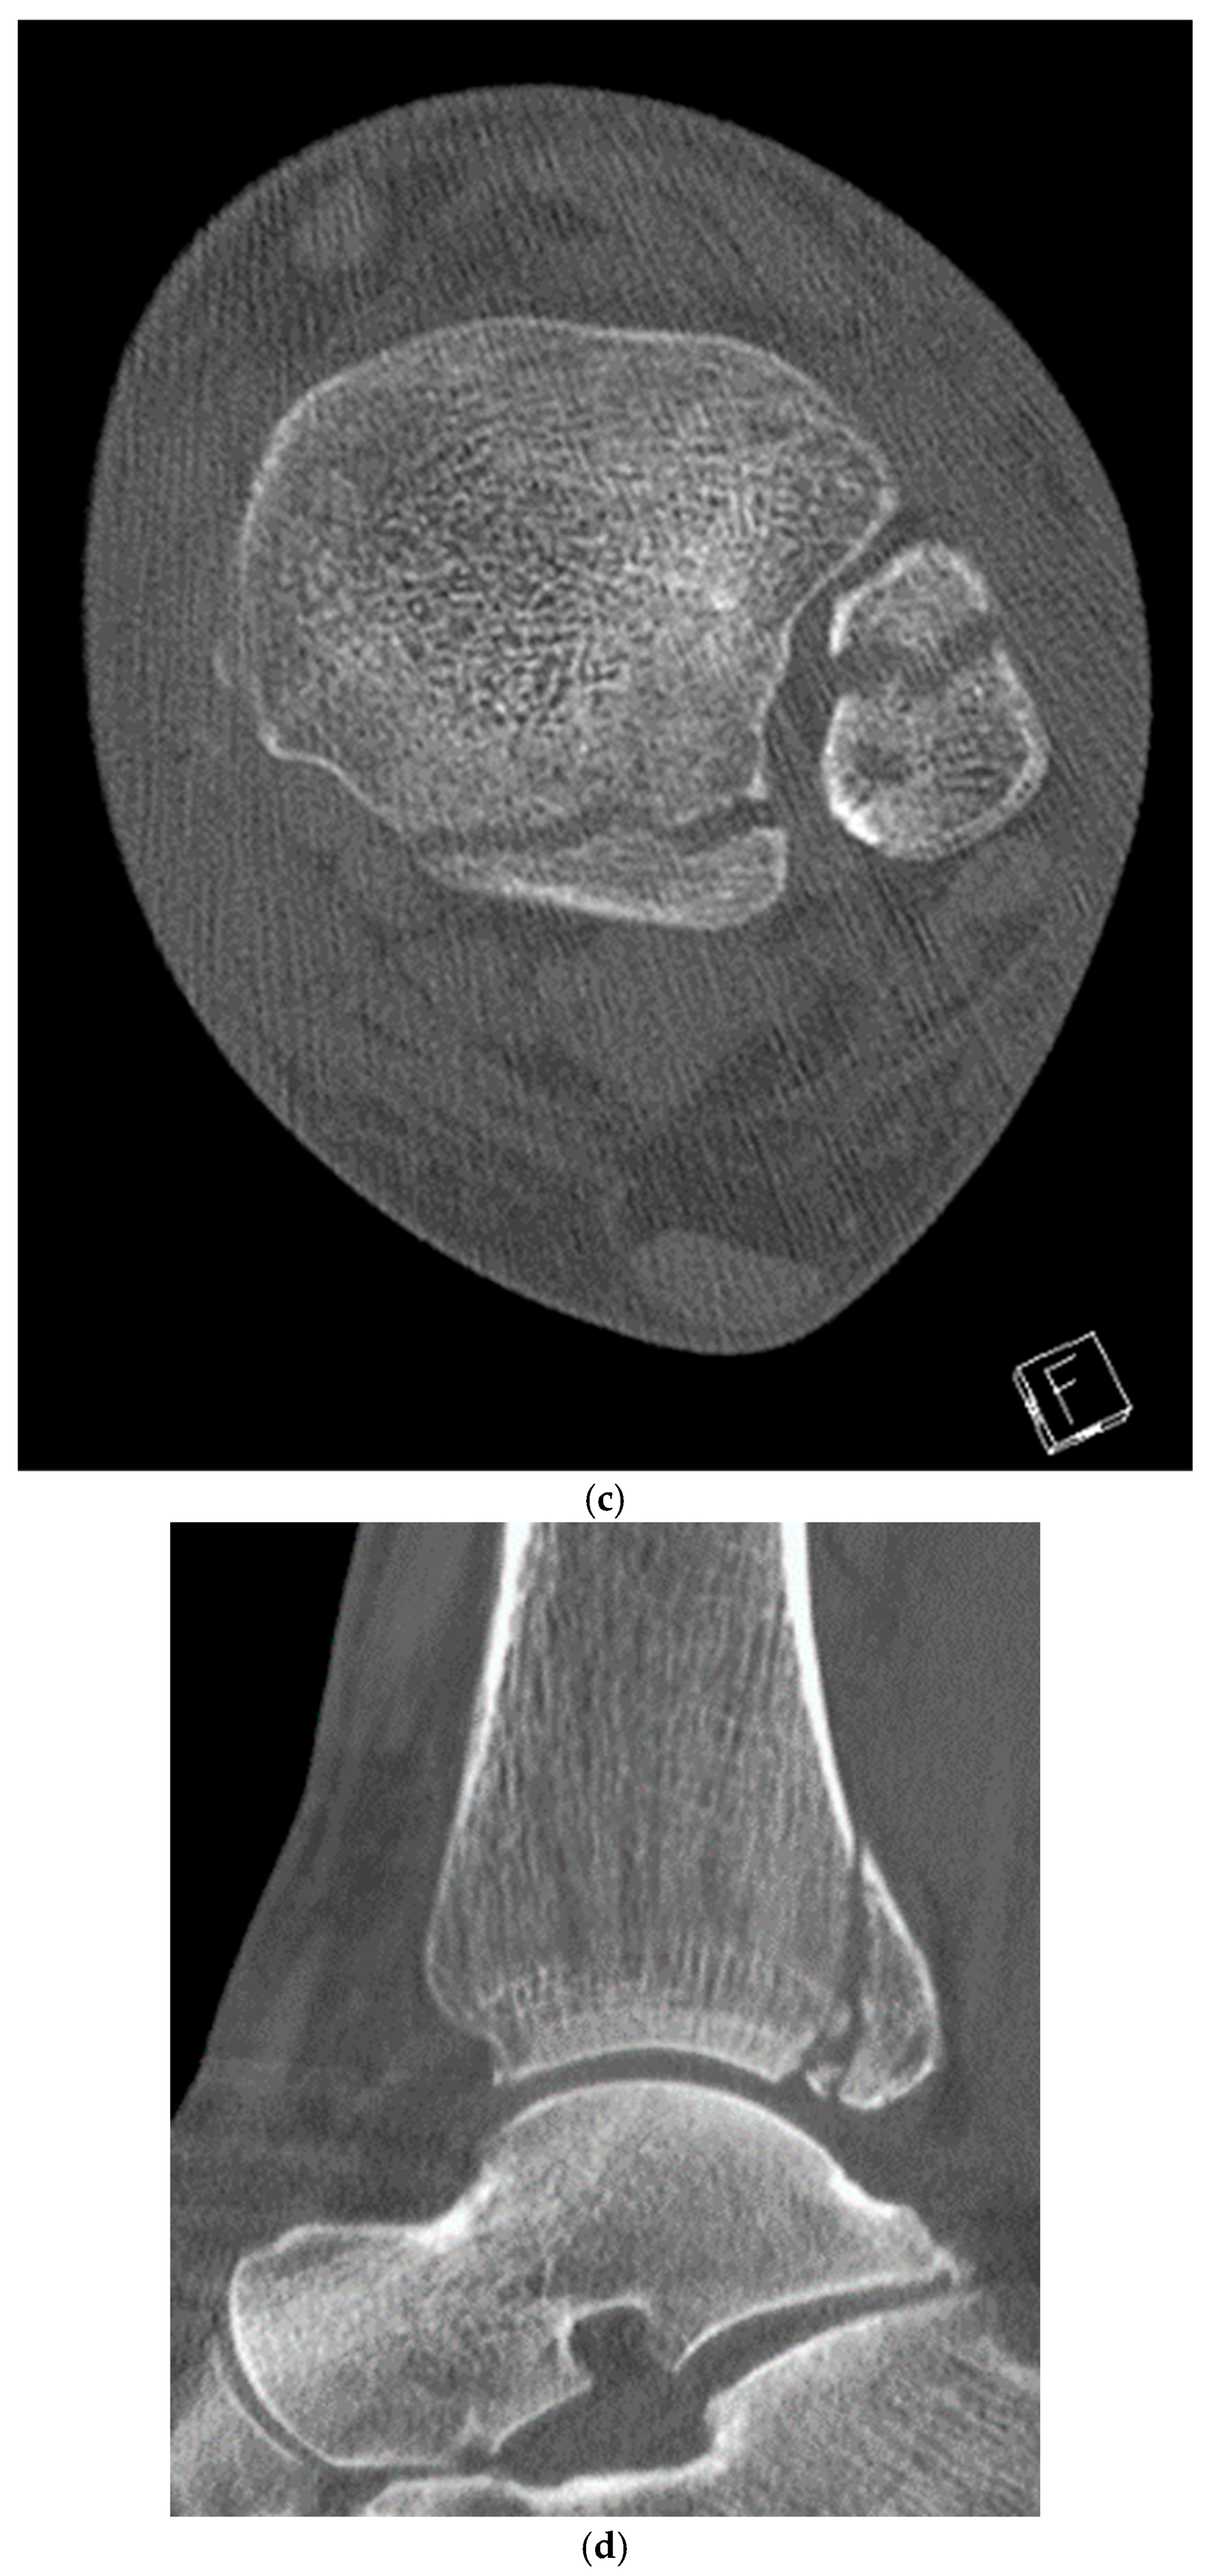

2. Preoperative Diagnostics

4. Classification

5. Case Description